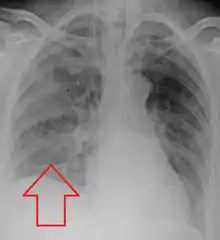

Aspiration pneumonia in a ventilated person with a central line and nasogastric tube

Aspiration pneumonia is typically diagnosed by a combination of clinical circumstances (people with risk factors for aspiration) and radiologic findings (an infiltrate in the proper location).[1] A chest x-ray is typically performed in cases where any pneumonia is suspected, including aspiration pneumonia.[18] Findings on chest x-ray supportive of aspiration pneumonia include localized consolidation depending on the patient's position when the aspiration occurred.[18] For example, people that are supine when they aspirate often develop consolidation in the right lower lobe of the lung.[18] Sputum cultures are not used for diagnosing aspiration pneumonia because of the high risk of contamination.[19] Clinical symptoms may also increase suspicion of aspiration pneumonia, including new difficulty breathing and fever after an aspiration event.[6] Likewise, physical exam findings such as altered breath sounds heard in the affected lung fields may also be suggestive of aspiration pneumonia.[6] Some cases of aspiration pneumonia are caused by aspiration of food particles or other particulate substances like pill fragments; these can be diagnosed by pathologists on lung biopsy specimens.[20]